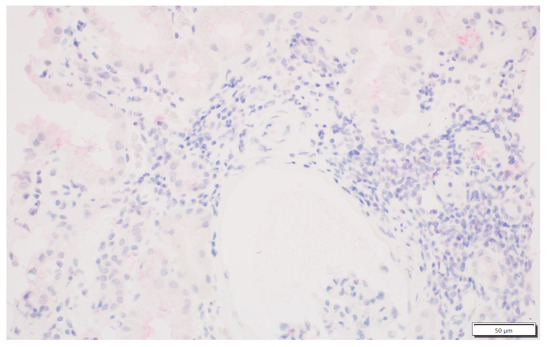

2.2. IDO1 Expression Analysis

3.2. Rejection Observed in Patients Displaying IDO1 Expression in Interstitial Foci

3.3. Analysis of Antibody-Mediated Rejection (AMR)

3.4. T-Cell-Mediated Rejection (TCMR) Analysis

3.5. Pure Types of Rejection